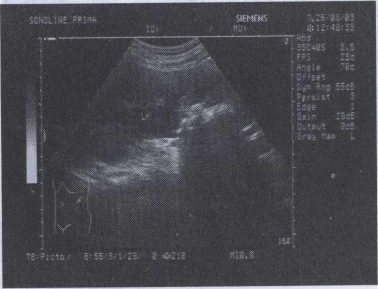

43.患者多处骨折,结合颈部超声图像,最可能的诊断是

35.患者颈部包块5年,结合超声声像图,最可能的诊断是